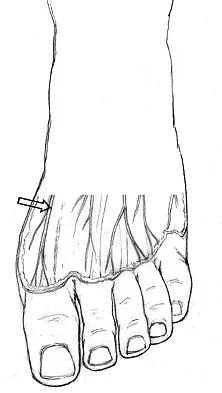

The dorsal digital cutaneous nerve of the great toe shown in Figure 8 is a branch of what nerve?

The dorsal digital cutaneous nerve of the great toe shown in Figure 8 is a branch of what nerve?